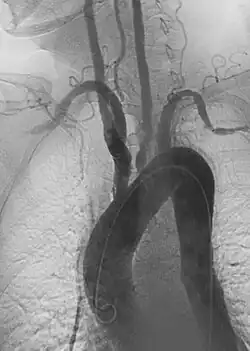

![]() Imagen angiográfica oblicua anterior izquierda de la arteritis de Takayasu que muestra áreas de estenosis en múltiples grandes vasos | ||

La arteritis de Takayasu también conocida como enfermedad sin pulso, tromboaortopatía oclusiva, síndrome del arco aórtico, es una enfermedad inflamatoria (vasculitis granulomatosa) de causa desconocida que afecta a la aorta y a sus ramificaciones, incluyendo la arteria carótida.[2] Aunque se han encontrado casos en todo el mundo, se muestra con frecuencia en mujeres jóvenes de Asia. Las mujeres con esta enfermedad superan en número a los hombres por 8 a 1, y la edad de comienzo se encuentra entre los 15 y los 30 años. En el mundo occidental, la arteriosclerosis es una causa más frecuente de obstrucción de los vasos sanguíneos.